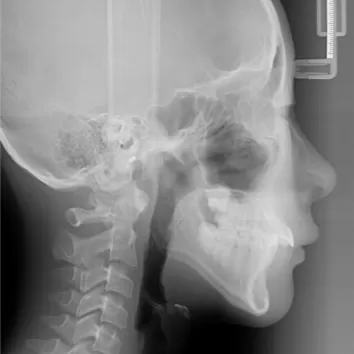

X-rays before treatment

[Panoramic Radiography/Lateral Cephalogram]